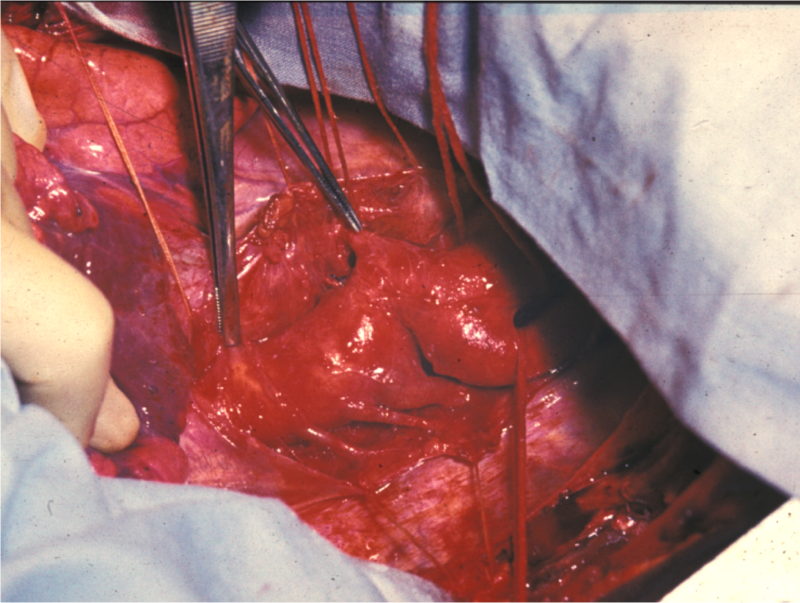

Treatment of large ventricular septal defect involves surgery.

Tetralogy of Fallot (ToF)

Tetralogy of Fallot (ToF) is a congenital cardiovascular anomaly that includes:

- Right ventricular outflow tract stenosis

- Right ventricular hypertrophy

- Ventricular septal defect (VSD)

- An overriding aorta